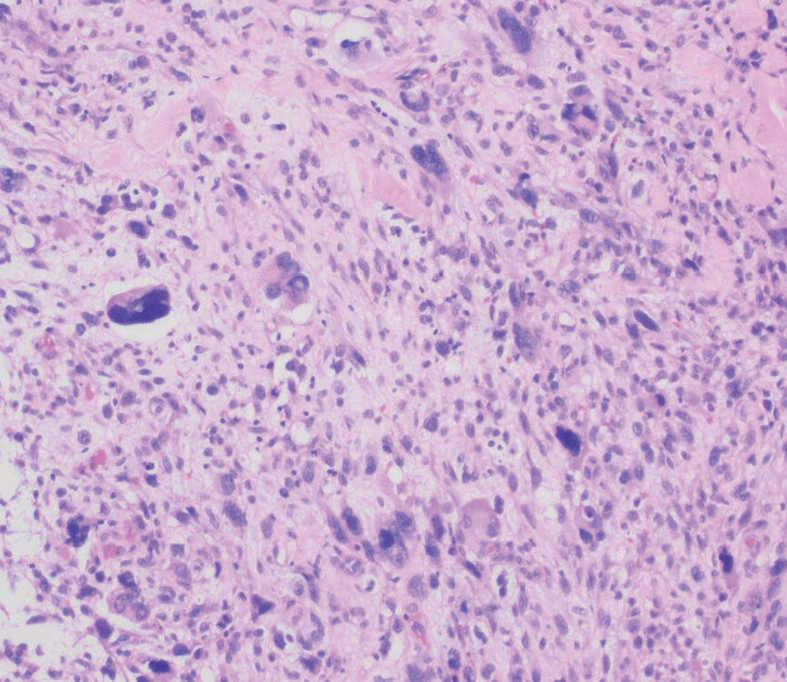

Fig. 3.--La neoplasia está constituida por células con núcleos pleomórficos, abigarrados. Destaca la presencia de células gigantes multinucleadas.

En el examen histológico se observó una neoformación celular de crecimiento difuso que abarcaba profundamente toda la dermis y el tejido celular subcutáneo, con efecto compresivo sobre la epidermis, que se encontraba adelgazada. Las células tumorales eran de aspecto pleomórfico, abigarrado, se acompañaban de algunas células gigantes multinucleadas y estaban dispuestas de forma desordenada. También infiltraban paredes vasculares y tractos nerviosos. Las células neoplásicas fueron S100 y vimentina positivas. El antígeno Ki-67 fue expresado en el 40 % de las células del tumor. El resto de técnicas inmunohistoquímicas realizadas fueron negativas, incluyendo HMB-45, citoqueratinas, actina, desmina, factor VIII, antígeno leucocitario común y enolasa neuronal específica.